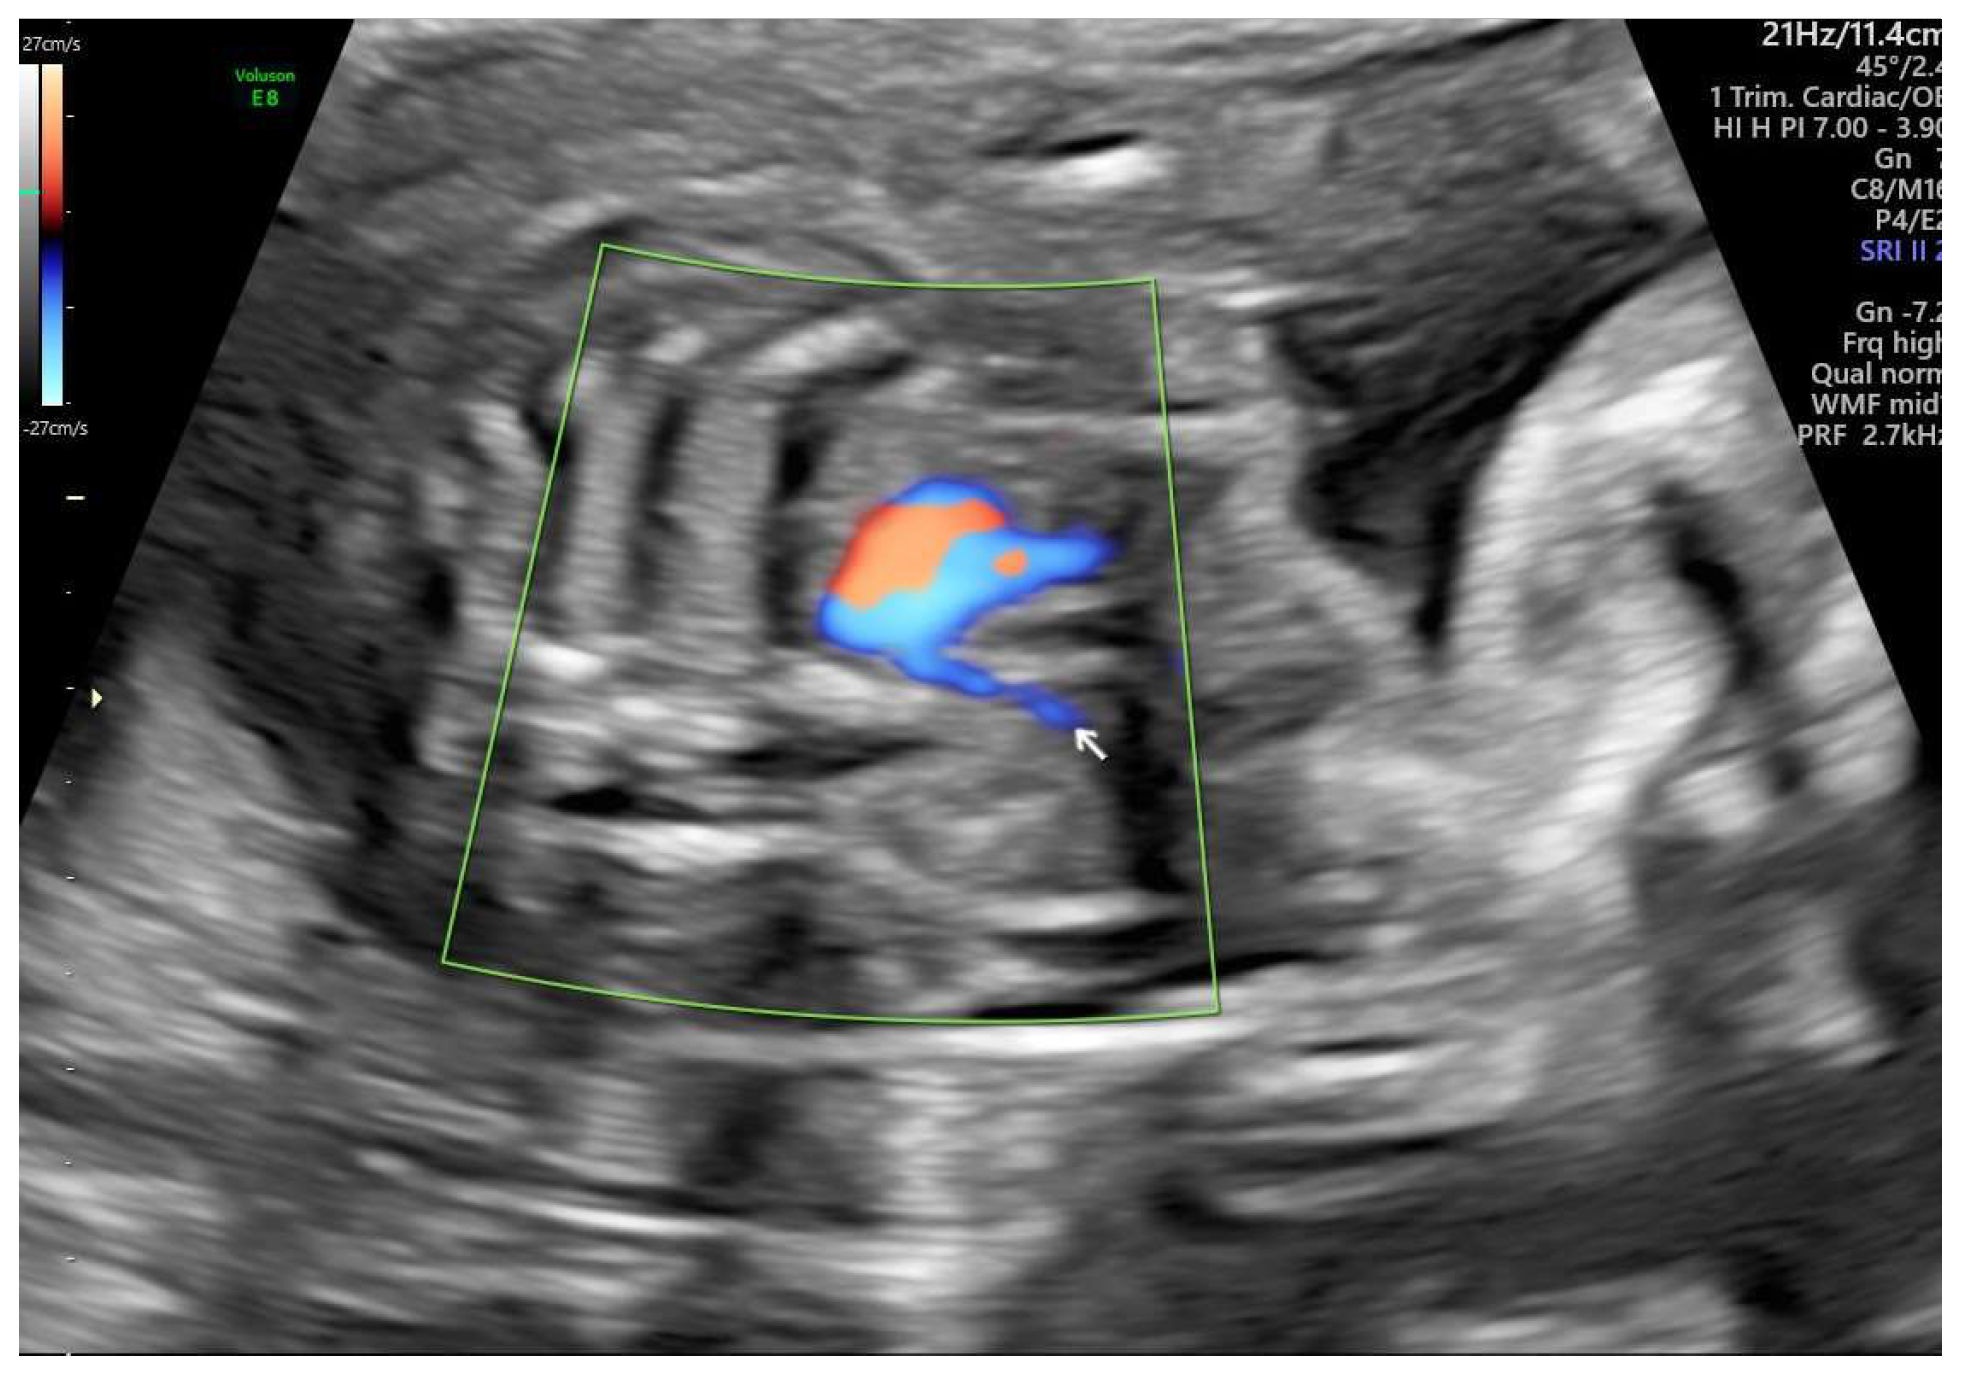

ARSA cases were identified during routine prenatal transabdominal ultrasonography of unselected patients at our hospital between July 2020 and June 2023. Grayscale and color Doppler ultrasonography in the transverse three-vessel view assessed the right subclavian arteries. The presence of ARSA in the transverse plane was meticulously confirmed by two operators with specialized experience using the GE Voluson E8 and S10 ultrasound machines. The examination was performed during the second trimester at a gestational age ranging between 21 and 23 weeks and adhered to the International Society of Ultrasound in Obstetrics and Gynecology guidelines for structures and detection techniques. ARSA incidence in the second trimester ranges from 0.4% to 1.5% in chromosomally normal fetuses [21]. The examination used a B-mode segmental view approach complemented by color Doppler ultrasonography with specific color Doppler velocity settings to enhance clarity. The ultrasonic findings are presented in Figure 1 and Figure 2 for reference.

Figure 1. Color Doppler ultrasound images of the fetal aberrant right subclavian artery at 22 weeks of gestation.